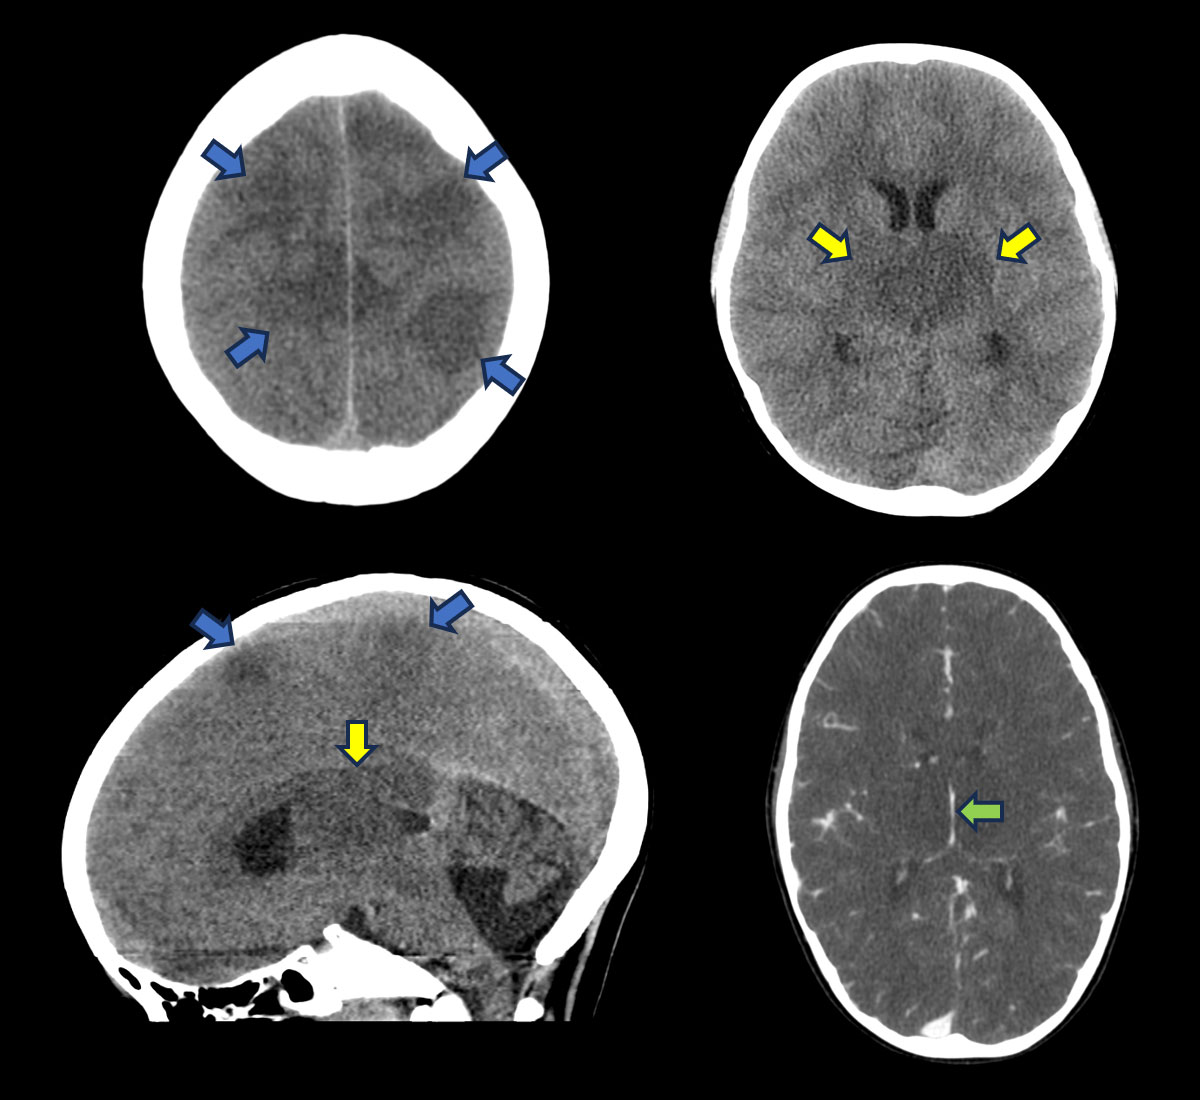

Noncontrast CT:

- Multifocal parenchymal densities involving both grey-white matter in a nonvascular distribution in the supratentorial brain (blue arrows).

- Diffuse bithalamic swelling and hypodensity (yellow arrows).

- Basal cisternal effacement and indistinct mamillopontine distance on sagittal sections

Contrast enhanced CT:

- Patent internal cerebral veins (green arrows).